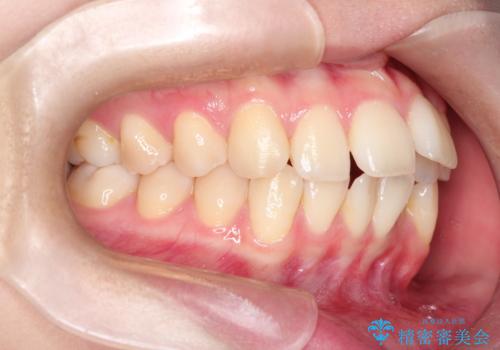

ワイヤーによる抜歯矯正でガタガタの改善

- 前歯のがたがたを主訴に来院されました。

上下の前歯が前方に傾斜しているのもあり、内側に前歯をひっこめるために上下左右の歯を1本ずつ抜歯して矯正することとしました。

ガタガタも改善しましたが、前歯が内側に引っ込むことにより口元もすっきりして、唇が閉じやすくなりました。